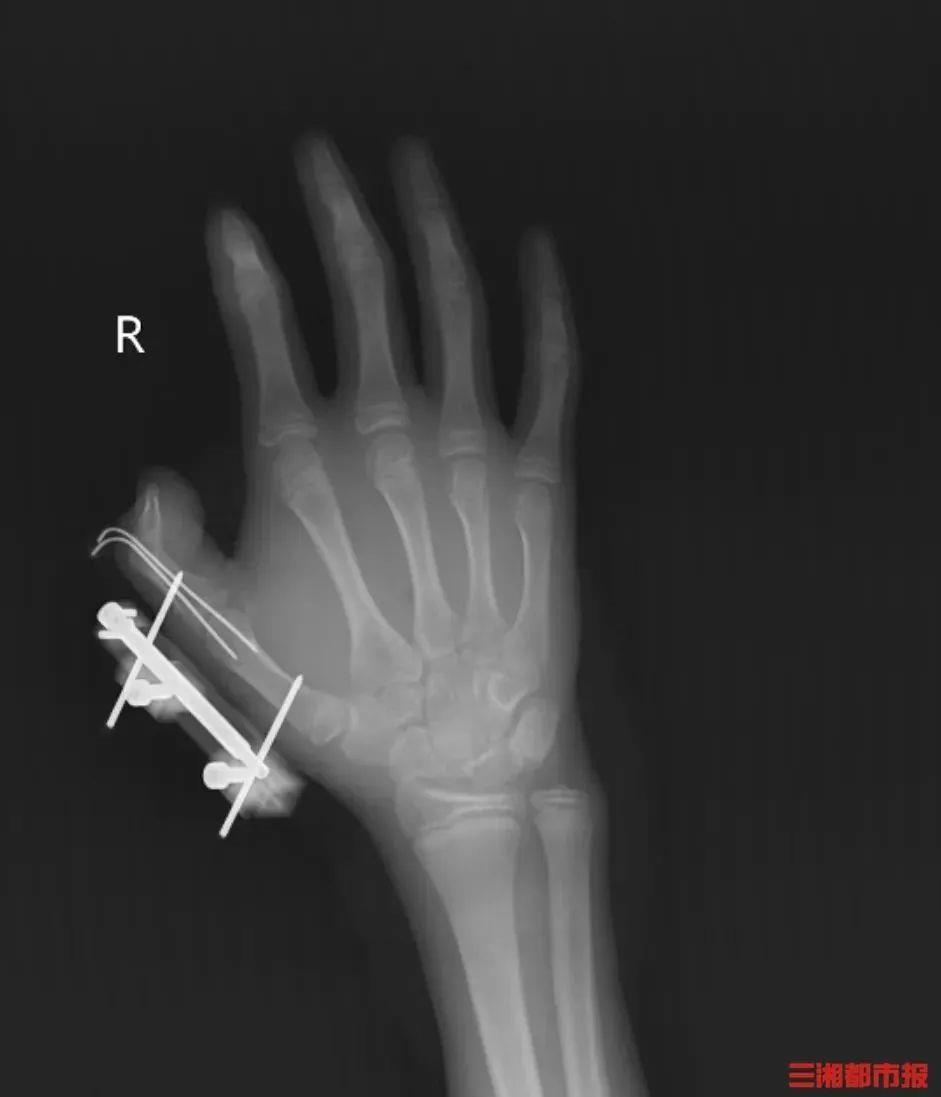

蓦然,密封袋里的干冰发生爆炸,维维的右手短暂鲜血直流,拇指虎口处被撕开放盘约10厘米的伤口,深可见骨,肌肉组织断裂外露,还伴跟着拇指骨折、枢纽脱位,扫数拇指完全失去知觉。

见状,家东谈主飞快带他到当地病院包扎,随后遑急转往湖南省东谈主民病院昆仲显微外科。经治疗,维维的拇指保住了,但后续还需弥远康复测验,智商逐渐收复手部精细算作功能。